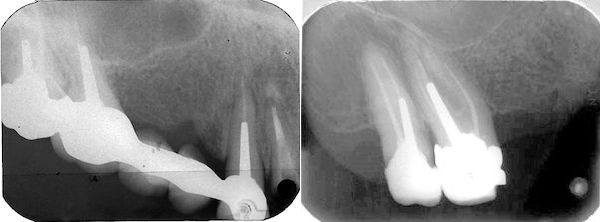

74-jährige Patientin (01.09.2022 / 404)

2022 zeigt ein CT eines Röntgeninstituts eine Perforation des Sinusbodens und eine direkte Verbindung zwischen dem Schleimhautpolster und der mesiobukkalen Wurzel des Zahnes 16. Leider wurde dies im Röntgenbefund nicht erwähnt. Wegen der unverdächtigen Röntgenbildes des Zahnarztes war die Patientin froh, dass der Zahn unverdächtig schien und sie ihn nicht extrahieren musste.

77-jährige Patientin (30.06.2025 / 404)

14 Tage nach der Extraktion war das Schleimhautpolster nur noch halb so gross:

09.07.2025 23.07.2025